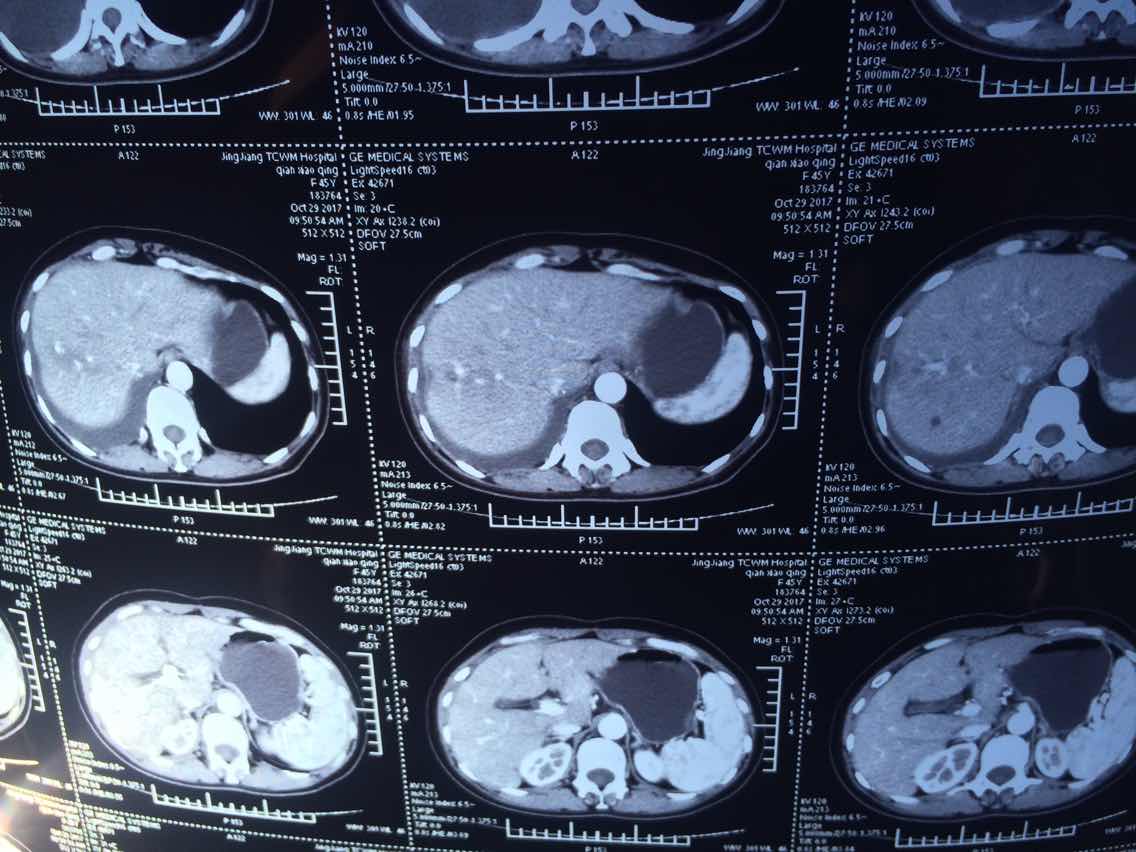

2017.10.29

2

3

4

5